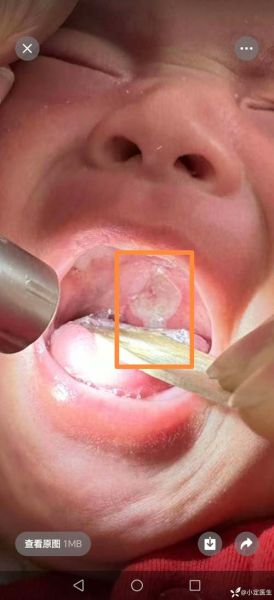

看图识溃疡:家长如何与鹅口疮、马牙区分?

不少家长把四个月宝宝口腔溃疡图与鹅口疮混淆,结果用错药。快速区分要点:

- 颜色:溃疡中心呈乳黄或灰白色,边缘红;鹅口疮为均匀奶块样白斑。

- 形状:溃疡边缘不规则,略凹陷;鹅口疮表面凸起,擦不掉。

- 痛感:溃疡一碰就哭;鹅口疮早期往往无痛。